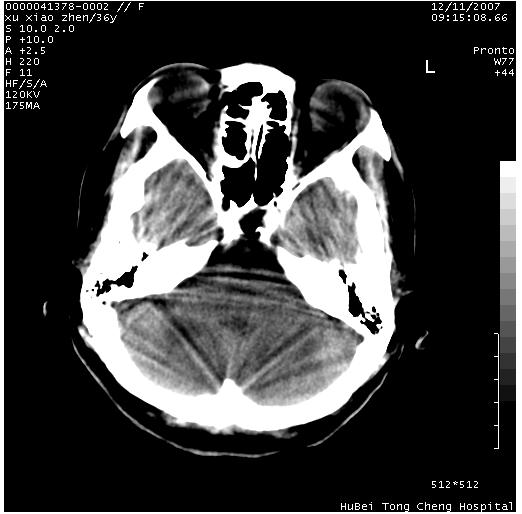

以下是引用wzr在2007-12-12 18:58:00的发言:[br]以脑白质受累,脑肿胀明显,脑室变窄,多考虑炎性改变,建议进一步ce或mri明确.

以下是引用wqs571018在2007-12-12 19:48:00的发言:[br]脑白质受累,脑肿胀明显,脑室变窄,多考虑炎性改变,脑膜炎可能性大;建议mri明确.。